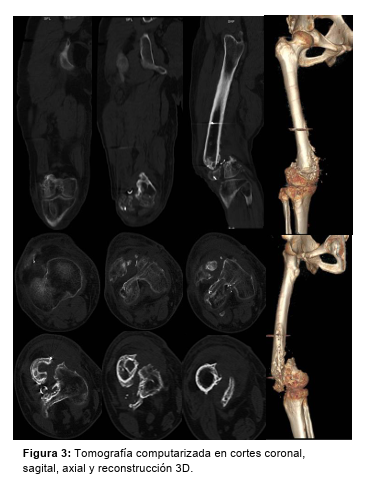

Se solicita tomografía axial computada (Figura 3) y se planifican las 2 etapas restantes.